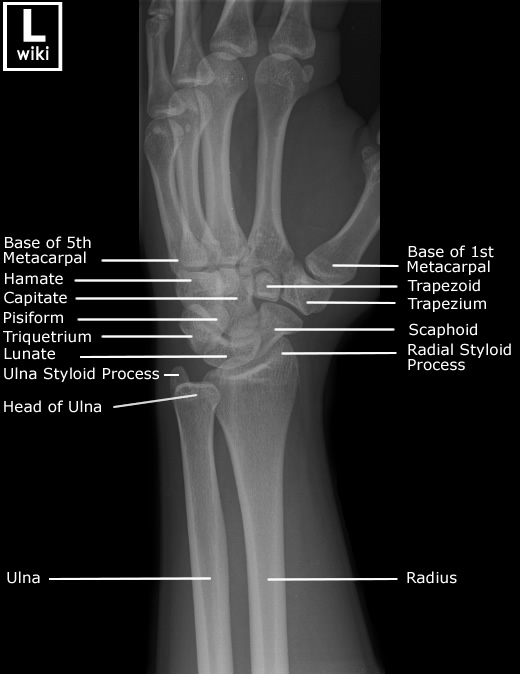

Wrist Radiographic Anatomy

| AP/PA View | Oblique View |

![]() |